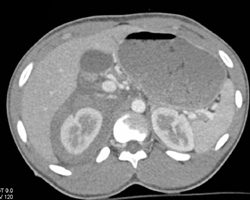

Diagnosis

Renal Laceration